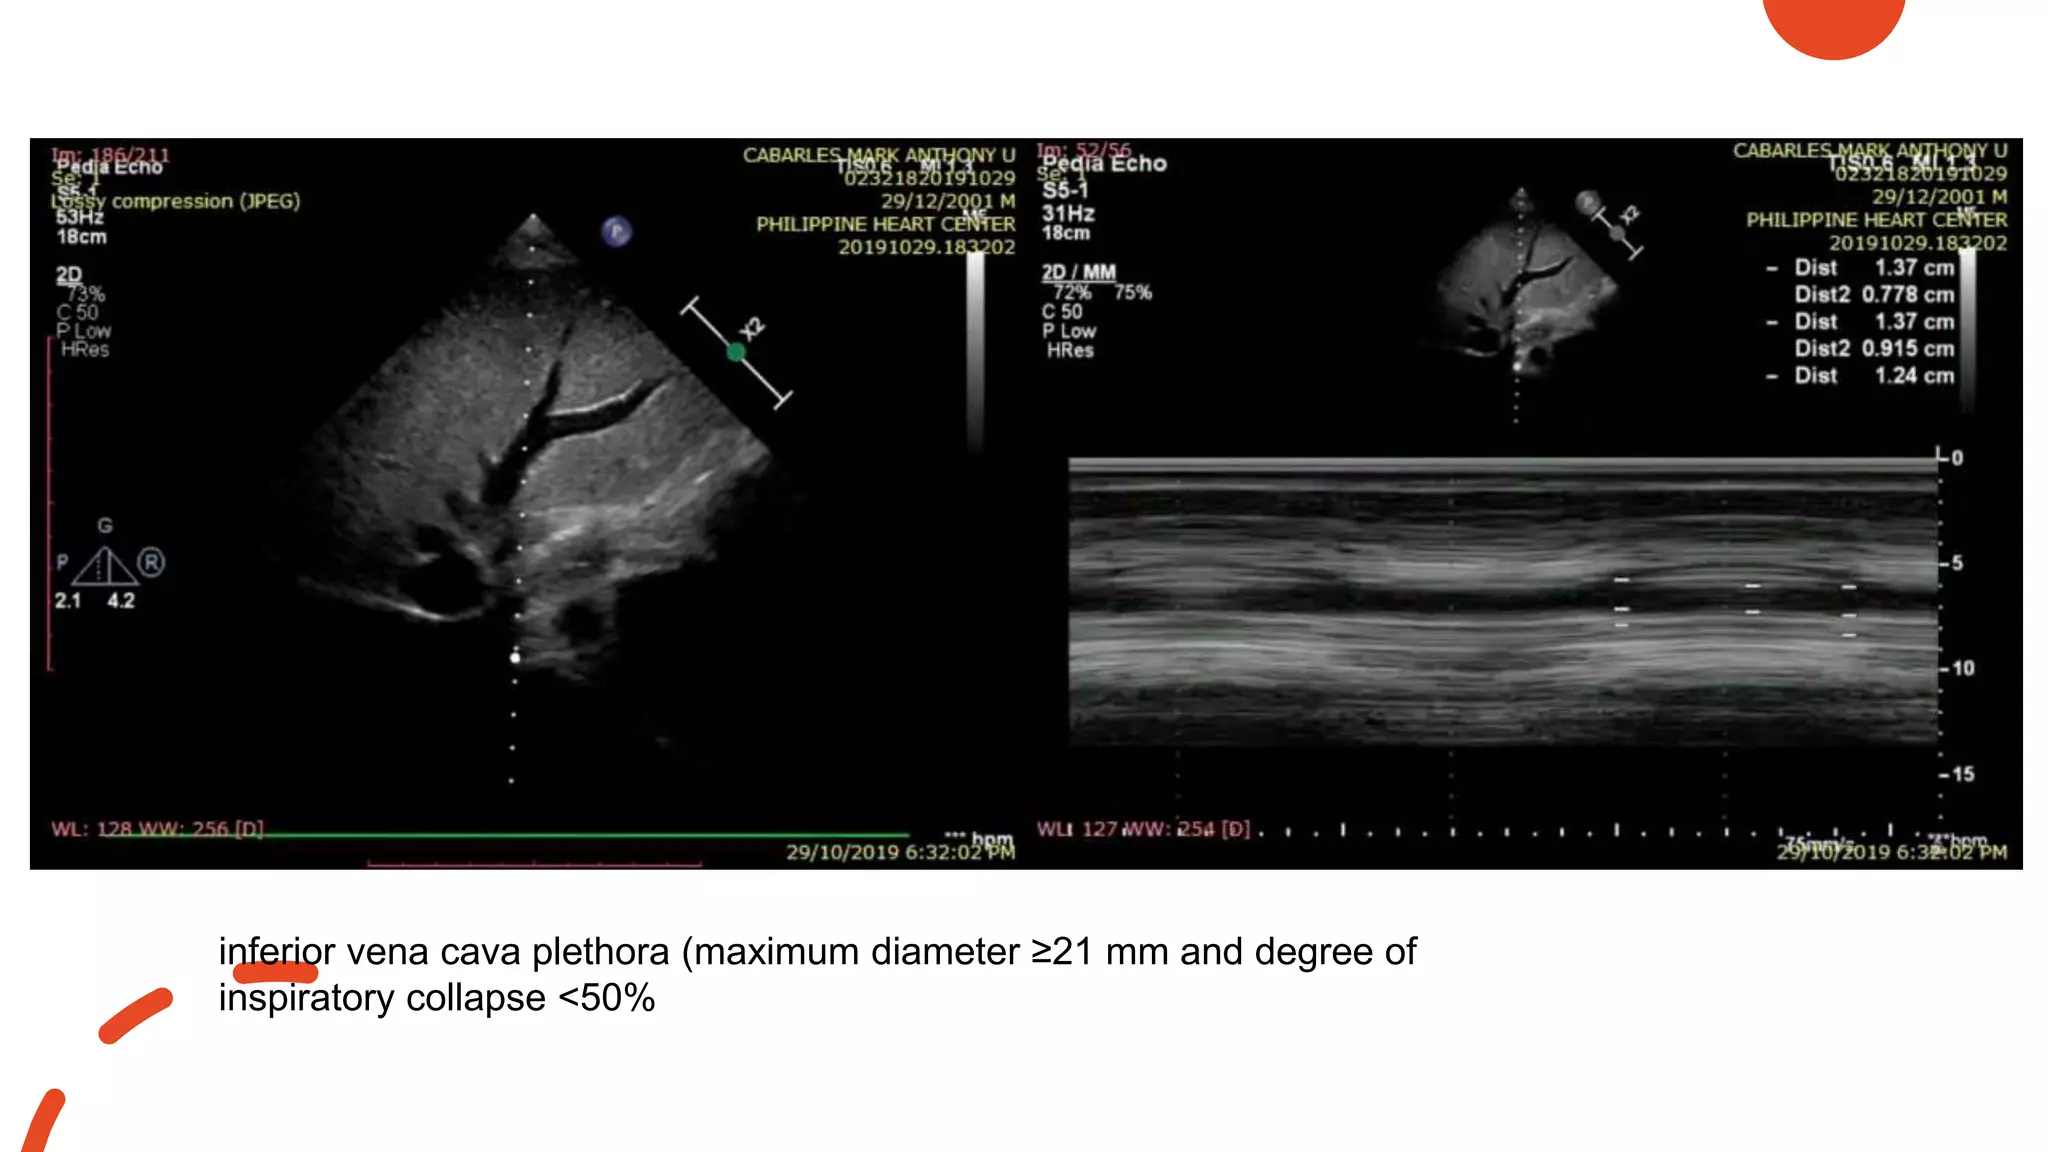

Septal Bounce

inferior vena cava plethora (maximum diameter ≥21 mm and degree of

inspiratory collapse <50%

Septal bounce • signof ventricular interdependence • ventricles are constricted (tethered by the pericardium)  motion of the ventricular walls is markedly reduced and the volume of the heart is fixed • Changes in ventricular volumes and pressures are then reflected through deviations of the septum

inferior vena cavaplethora (maximum diameter ≥21 mm and degree of inspiratory collapse <50%